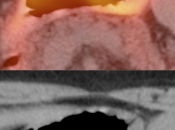

The difficulty with PET/CT imaging and gastric cancer is that it is both easy to overlook and easy to over-call.

Normal FDG uptake involving the stomach can be extremely variable. It is not uncommon to see diffuse intense uptake throughout the entire stomach or intense uptake limited to only a segment of the stomach (fundus, body or antrum).

• Focal or regional hypermetabolic activity is accompanied by at least the suggestion of associated wall thickening (often difficult to assess if the patient’s stomach is suboptimally distended with water or oral contrast);

• Uptake is extremely focal (more likely to represent malignancy or ulcer);

• Focal/segmental uptake is extremely intense.

• Hiatal Hernia: Increased metabolic activity is frequently encountered within a hiatal hernia. Such uptake is nearly always physiologic or inflammatory. Malignancy, however, sometimes cannot be excluded and upper endoscopy may be required.